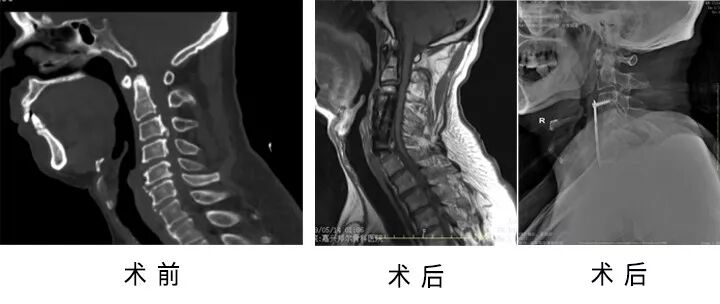

64歲的范大爺,十余年前出現(xiàn)右側(cè)肢體酸痛,5年前出現(xiàn)四肢無力,行走不穩(wěn),8個月前因行走不穩(wěn)跌倒后癥狀加重?zé)o法獨自行走,生活難以自理。

家屬帶著范大爺找到了省級知名骨科專家、邦爾骨科集團首席專家、嘉興邦爾骨科醫(yī)院院長趙凱教授,經(jīng)檢查,診斷為“脊髓型頸椎病,頸椎后縱韌帶骨化癥”。

趙凱教授帶領(lǐng)脊柱外科團隊為其進行了“前路頸3/4、4/5、5/6椎間盤切除+頸4、5椎體次全切除減壓+人工椎體植入+鈦板內(nèi)固定術(shù)”。術(shù)后范大爺右側(cè)肢體肌力明顯恢復(fù)。

術(shù)前術(shù)后對比圖